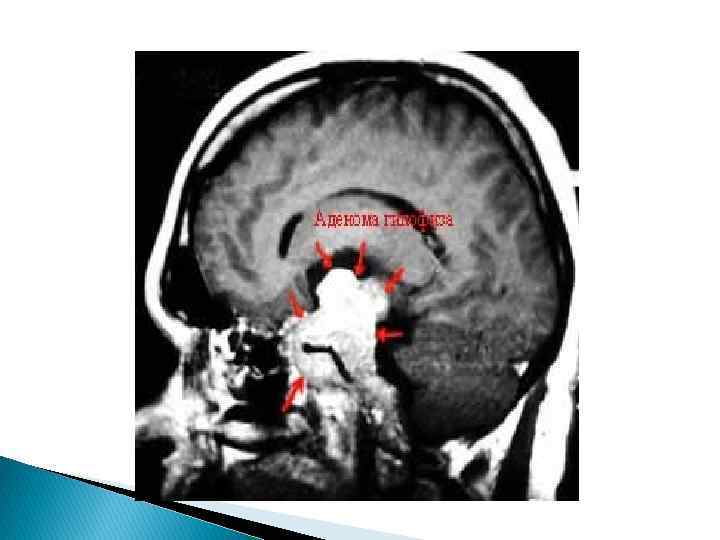

Рис. 2. 4. Магнитно-резонансная томография гипоталамо-гипофизарной области: а - норма (сагиттальная проекция); б - макроаденома гипофиза (сагиттальная проекция) Использование контрастных веществ значительно увеличивает диагностические возможности МРТ. Важным преимуществом МРТ является отсутствие лучевой нагрузки и, таким образом, возможность многократного динамического обследования пациента.

Достаточно информативным методом визуализации гипофиз является компьютерная томография. Рентгеновское КТисследование головы позволяет выявить изменения плотности гипофиз и, следовательно, дифференцировать микро- и макроаденомы «пустое» седло и кисты от нормальной ткани гипофиза. Тем и менее патология хиазмально-селлярной области трудна для диагностики с помощью КТ-исследования из-за наличия артефакта и невозможности дифференцировать небольшие патологически образования, рентгенологическая плотность которых близка к плотности цереброспинальной жидкости или нормальной мозговой ткани Доза рентгеновского излучения является тем фактором, которые ограничивает возможность многократного исследования и для тельного динамического наблюдения. Методом выбора визуализации гипофиза и гипоталамуса, а так же методом выбора топической диагностики новообразований гипоталамо-гипофизарной области является МРТ-исследование. Нормальный гипофиз на МРТ имеет очертания эллипса. МРТ позволяет различить стебель гипофиза, инфундибулярнуи ямку 3 -го желудочка, малейшие изменения структуры гипофиза наличие кистозного компонента опухоли, отдельные кисты, кровоизлияния, кистозное перерождение гипофиза.

Магнитно-резонансная томография — основной метод диагностики, позволяет выявить аденомы размерами менее 5 мм, однако, даже с учётом этого, примерно у 25 — 45% пациентов визуализировать аденому не удаётся. Компьютерную томографию применяют только в экстренных ситуациях при невозможности провести магнитнорезонансной томографии для исключения тяжёлых осложнений.